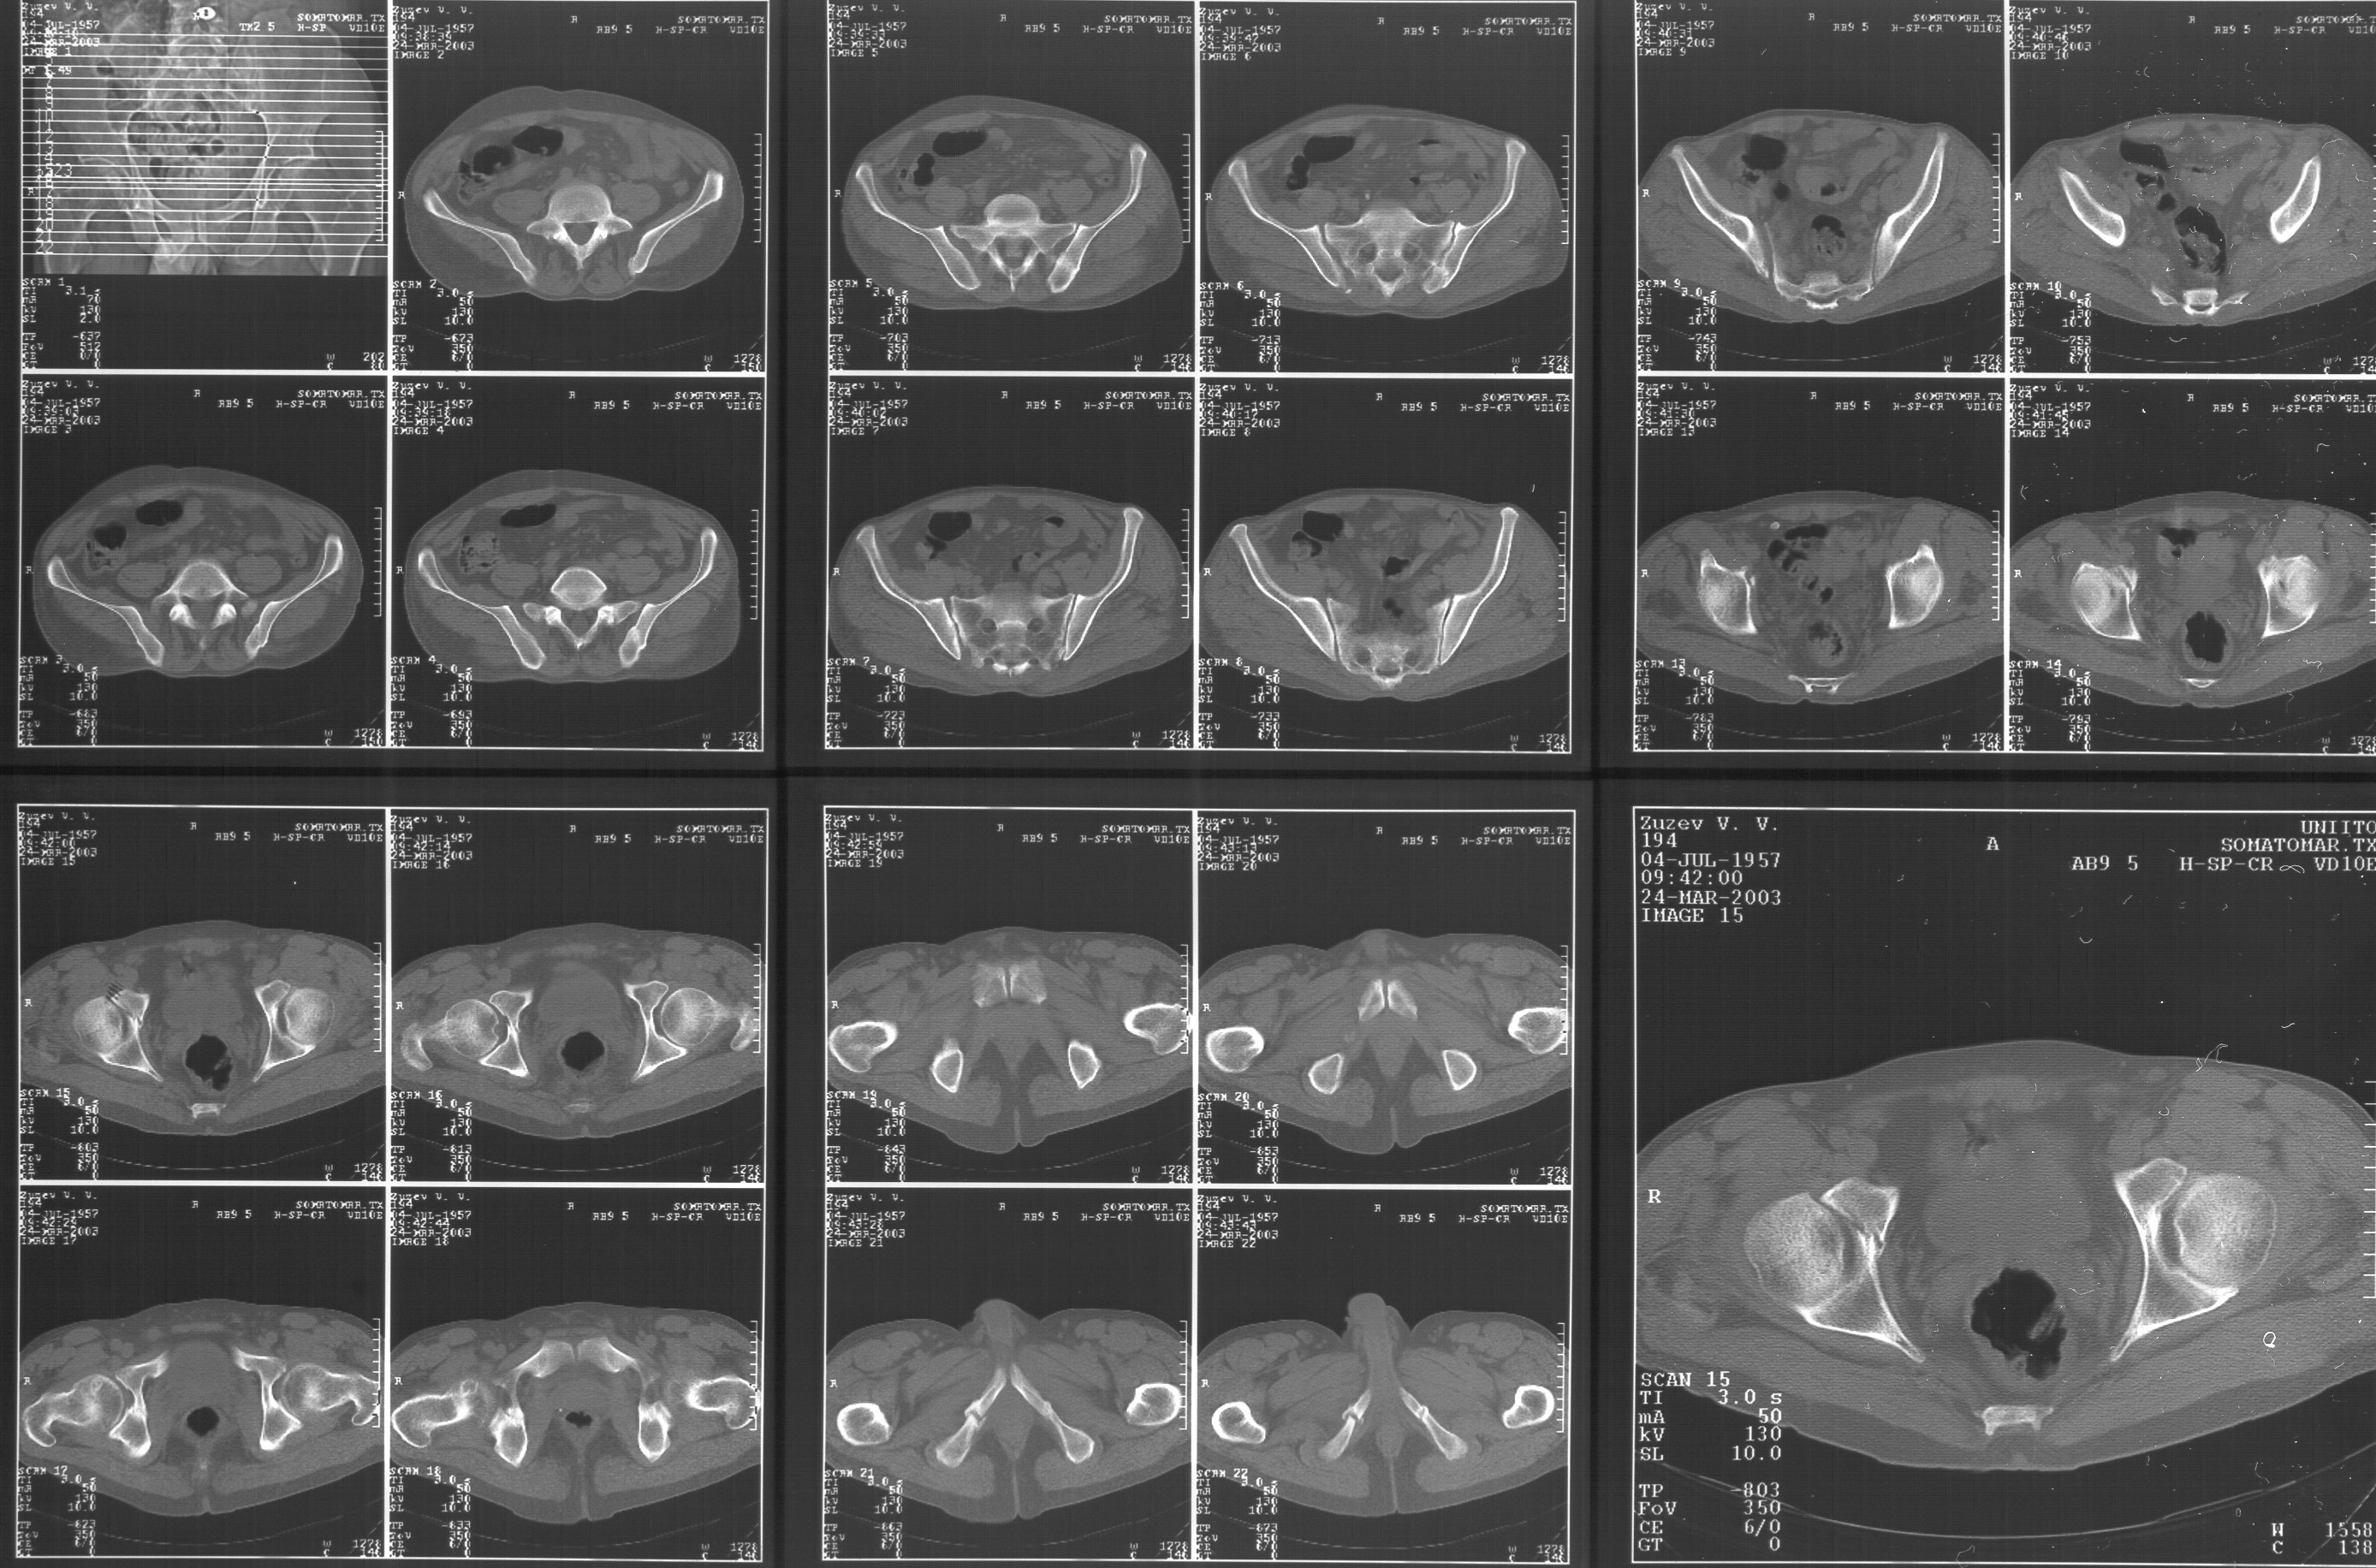

Прилагаю свежую КТ таза.

Буду признателен за комментарии и предложения по тактике.

Картинки см. ниже, левая - с экранным разрешением, вторая - полноразмерная, ~900 кб.

КТ в экранном разрешении

Полноразмрная картинка, около 900 кб

Based on the CT images you provided, he appears to have a nonunion of the the right ischium, which would explain his symptoms. General principles of treatment of hypertrophic (which this appears to be) nonunions suggest rigid fixation, but I'm not sure what the best approach would be. Could get a lag screw across the fracture through a Kocher-Langenbeck approach or plate osteosynthesis through direct ischial approach, but perhaps Chip, Adam or someone with more pelvic fracture experience could enlighten us all.

I think the CT cuts in question are on the right of the bottom row i.e.

http://www.hwbf.org/hwb/conf/alex47/image3a.jpg

Thanks for the link to the plain films and CT images.

I think this is just a pelvic ring disruption that has gone on to a non-union. The arrow is pointing to the inferior ramus non-union, and

the sup ramus is a high "root" fracture, right near the pecten. The sup ramus fracture enters the tab - you could call it an acetabular

fracture - but down here in Dallas we treat these acutely as stable pelvic ring injuries. The fracture in the anterior portion of the

acetabulum is so low it doesn't seem to cause much trouble.

His R sacroiliac joint is opened anteriorly a little bit - the "unreduced posterior lesion" Alex mentioned in his first post. My earlier post about plating, bone grafting, etc., is all wrong.

What you have is a pelvic fracture that hasn't healed after 4 months or so, with a minimal deformity.

I think what I would offer the guy is a percutaneous iliosacral screw to stabilize and improve the SI joint alignment, coupled with a perc anterior column screw to stabilize the high ramus fx. These screws aren't easy to place, and have a host of potential problems and complications. But, I think they would work.

Как Вы сами видели на томограммах, грубых деструктивных явлений крестцово-подвздошного сочленения не определяется( маркировка правая -левая сторона не видна), определяется сравнительно незначительное расширение суставной щели с одной стороны и не более того.

Виноват, первый раз не обратил внимания на возможность полноформатного просмотра томограмм. В этой связи -дополнения к своему первому комментарию: сросшийся перелом вертлужной впадины справа, L5-S1 спондилоартроз, расширение суставной щели крестцово-подвдзошного сочленения справа может компрометировать его стабильность и вызывать локальные боли, но вряд ли это может давать двусторонние проявления в нижних конечностях. Все-таки миелограмма или ЯМР желательно иметь, чтобы определиться в тактике.